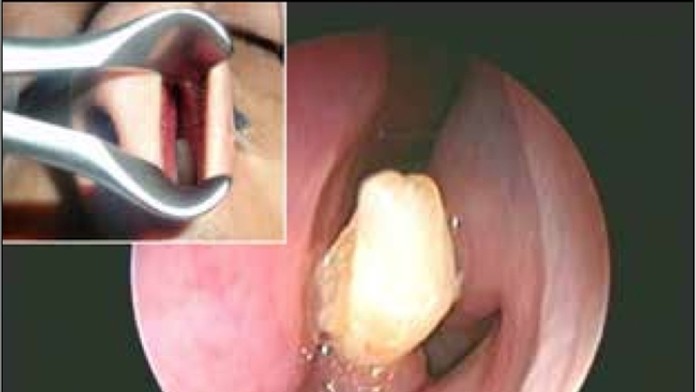

Zub v nose

Zdroj: American Journal of Case Reports

Lekári napokon preskúmali jeho nosnú dutinu. Narazili na niečo, čo doteraz ešte nikdy nevideli. Mladíkovi sa do nosa prerezal zub známy ako rezák.

Mladíkovi sa vyvinul rezák navyše a rástol mu smerom nahor. Museli mu ho operačne odstrániť.